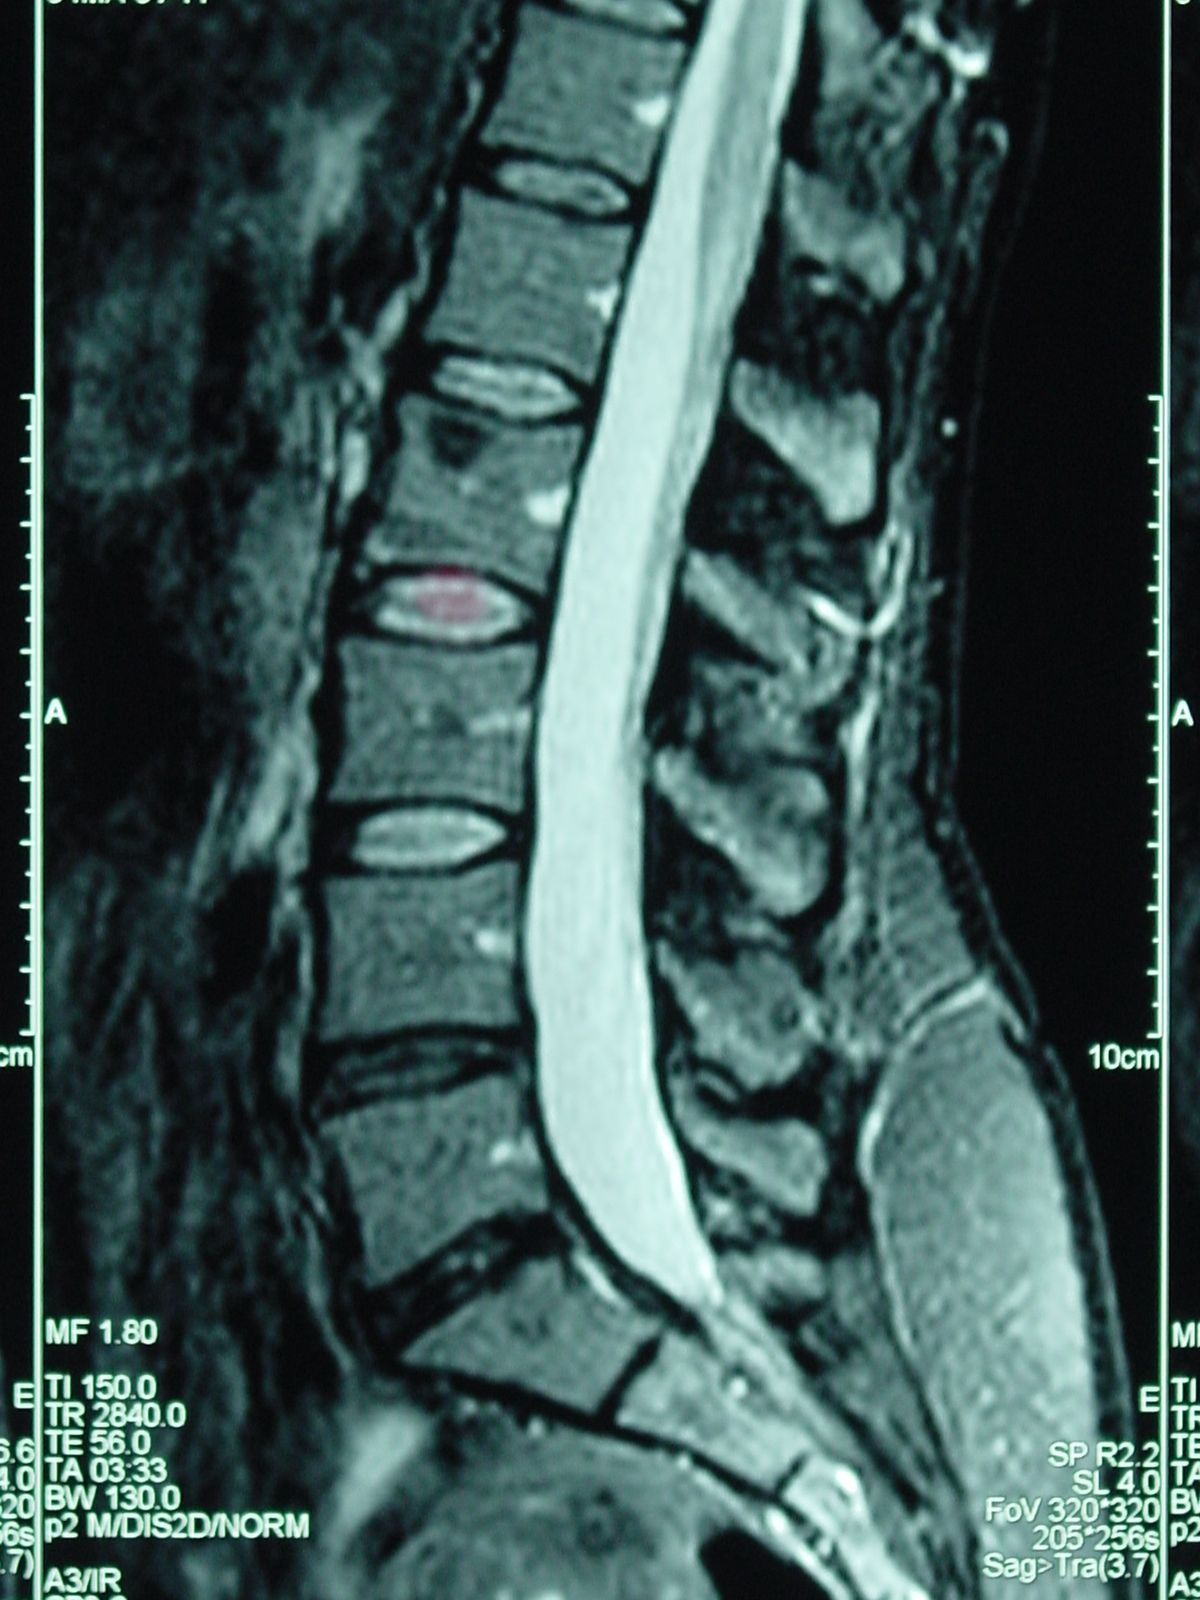

At your first visit, your doctor may recommend an x-ray or MRI to pinpoint the specific areas of damage and discomfort. Using this information, your doctor will determine your course of therapy and whether you are a candidate for Spinal Decompression (SD).